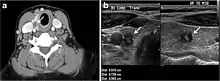

Fig. 7. A 51-year-old female patient post total thyroidectomy for PTC with elevated thyroglobulin measurement. an Axial non-enhanced CT scan of the neck at the level of the thyroid bed demonstrates a well-defined, rounded, homogenously dense soft tissue situated between the trachea and left internal jugular vein (white arrow). b Transverse ultrasound image of the neck demonstrates a well-defined, homogeneous, hypoechoic soft tissue nodule measuring 6 mm (white arrow) with no detected micro-calcifications. Biopsy showed a predominantly residual normal thyroid tissue with micro-foci of PTC.[1]

Fig. 8. A 48-year-old male patient post total thyroidectomy with PTC recurrence. a Transverse greyscale ultrasound of the neck demonstrates a left thyroid bed heterogeneous, predominantly hypoechoic irregular lesion with calcifications (white arrow). b A spot image of iodine 123 total body scan of the neck demonstrate a focus of abnormal radiotracer uptake at the left thyroid bed (Black arrows) between the annotated markers. c Enhanced axial CT scan of the neck demonstrates an enhancing large left thyroid bed mass (white arrow) with no calcifications. The lesion exerts a mass effect on the oesophagus (black arrow) and is inseparable from the trachea.[1]

Fig. 9. A 58-year-old male patient with persistence PTC at thyroid bed with hypervascular nodal metastasis. a–c Transverse greyscale and colour Doppler neck ultrasound demonstrate hypoehoic soft tissue in the left thyroid bed (white arrow in a). There are a heterogeneous enlarged lymph nodes at level 2 and 3 with markedly increased vascularity (white arrow in b and c). d–f Enhanced axial CT images of the neck demonstrate a 2.7 × 1.4 cm hypodense soft tissue lesion anterior to the left carotid sheath (white arrow). There are left-sided enhancing abnormal and enlarged lymph nodes at cervical level 2 and 3 (black arrows).[1]